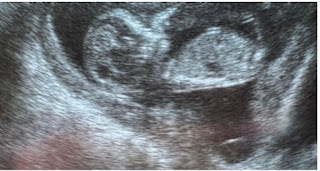

Dejo un vídeo precioso explicativo de la Clínica Universidad de Navarra, vía You-Tube, desde el momento en que comienza todo:

Cuando, gracias al amor de los padres, un óvulo es fecundado por un espermatozoide, con ese destello de luz increíble, se forma un nuevo ser. Ya no son células del padre y de la madre, ni un nuevo “tejido”, sino una nueva persona, con un mar amplio y casi infinito de posibilidades. Y se le denomina “cigoto”. Algo tan valioso en sí mismo.

Y dejo otro vídeo espectacular desde el primer momento de la fecundación, con ese esplendor de luz...